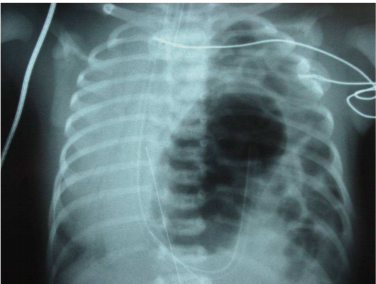

46. 一個剛出生的嬰兒有呼吸窘迫的現象,胸部X光顯示如下,對此病人的處置下列何者錯誤?

(A)氣管內插管(endotracheal tube) (B)放置胃管 (C)面罩呼吸 (mask) (D)給與動脈及靜脈導管